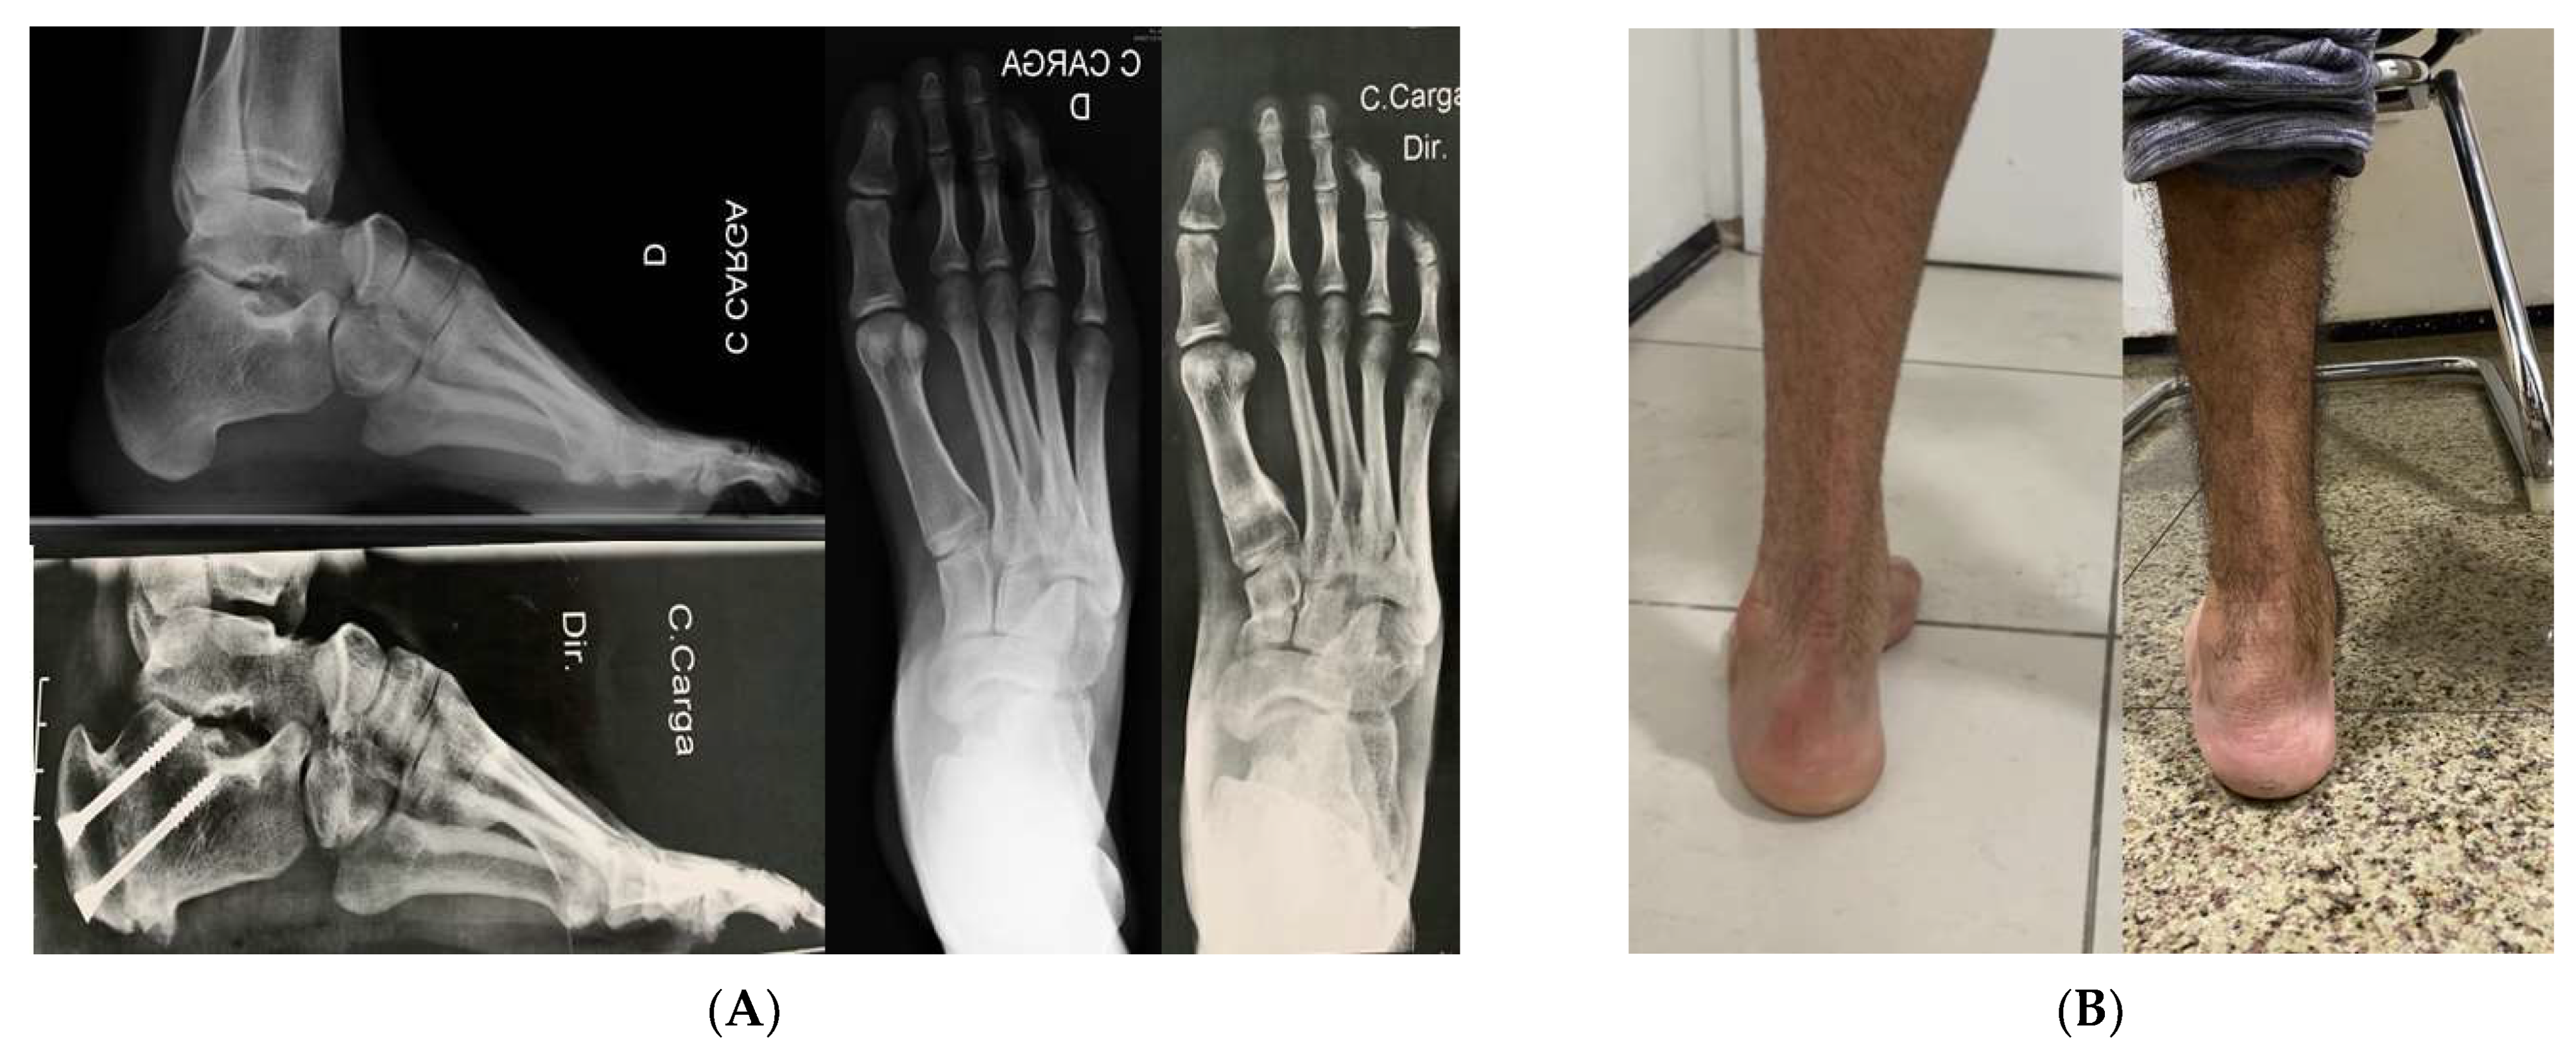

One patient with a Charcot sequela deformity evolved to delayed consolidation with screw fracture (Figure 4). Three cases (15%) evolved to incomplete correction, but only one (33.33%) required additional surgery. These incomplete correction cases belonged to the initial cases. No wound complications or non-consolidation of the cuboid bone or first metatarsal osteotomies were observed. (Figure 5).

Patients’ initial complaints resolved completely, as the median follow up time until this report was small (4.2 months) some unspecific complaints related to the rehabilitation program were still present especially muscular pain on long distance walks and non-painful limp.

Figure 5. (A) We had full consolidation of cuboid and first metatarsal bones without fixation and with immediate weight bearing. (B) Clinical improvement of hindfoot alingment.